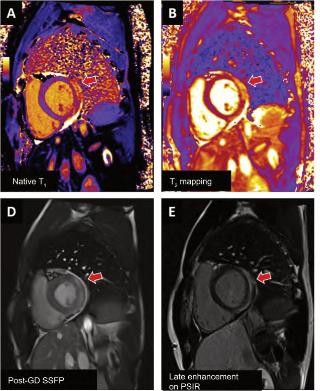

Lamiocarditisesunainflamacióndel músculodelcorazón(miocardio). Puedesercausadaporvariasenferme‐dades,infeccionesviralesobacterianas,tra‐stornosautoinmunitarios,exposiciónatoxi‐nas,entreotrosfactores.

¿CUÁLESSURELACIÓNCONLACOVID-19?

EnelcontextodelapandemiadeCOVID-19,se hainformadodecasosdemiocarditisaso‐ciadosalainfecciónporelvirusSARS-CoV-2. Secreequeestopuededebersealarespuesta inmunitariadelcuerpoalainfección,que puedeprovocarinflamaciónenvarios órganos,incluidoelcorazón.

Tambiénsehainformadodecasosmuyraros demiocarditisdespuésdelavacunación contraCOVID-19,especialmenteenpersonas jóvenesdespuésderecibirlavacunadeARNm (Pfizer-BioNTechyModerna).

Aunquesenecesitamásinvestigaciónpara comprendercompletamentelarelaciónentrela miocarditisylavacunaCOVID-19,losexpertos hanseñaladoquelosbeneficiosdelavacu‐

nacióncontraCOVID-19superanconcreces losriesgosdeefectossecundariosgraves.

Esimportantedestacarquelamiocarditises unaafeccióngravequepuedeponerenpeligro lavida,pueslamortalidadpuedellegaraserha‐stadel20%encasodenosertratadaatiempo, yelmétodonoinvasivomásadecuadoparasu diagnósticoeslacardiorresonancia.

Siexperimentasíntomascomodolorenel pecho,dificultadpararespirar,palpitaciones ofatigadespuésdelavacunaciónolainfec‐ciónporCOVID-19,debebuscaratenciónmé‐dicadeinmediato.

¿Porquéestáasociadaaunainfección ovacunadeCovid,SARS-CoV-2?Resonanciamagnéticaybiopsiaendomiocárdica